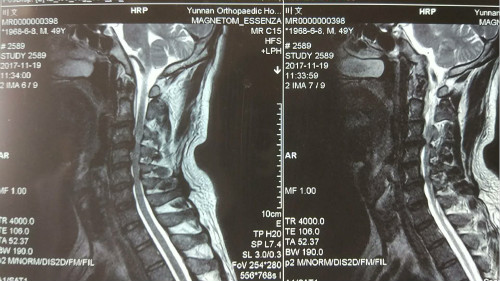

术前核磁共振显示C34椎间盘突出压迫脊髓致其变性

看到漂亮的术后X光片,体会到麻醉醒后立竿见影的手术效果,叶先生兴奋不已。就在进手术室前,电视台记者采访他时,他的左手还不能用力抓握,右手更是无法握拢,而术后一觉醒来,他两只手都可以握住甚至抓牢主刀医师董谢平的手了;术前的蹒跚步态也变得稳健了。晚上来看望他的家人走到近前发现站在走廊上与医生交谈的病人竟然是他们的亲人时,都惊喜得合不拢嘴来。